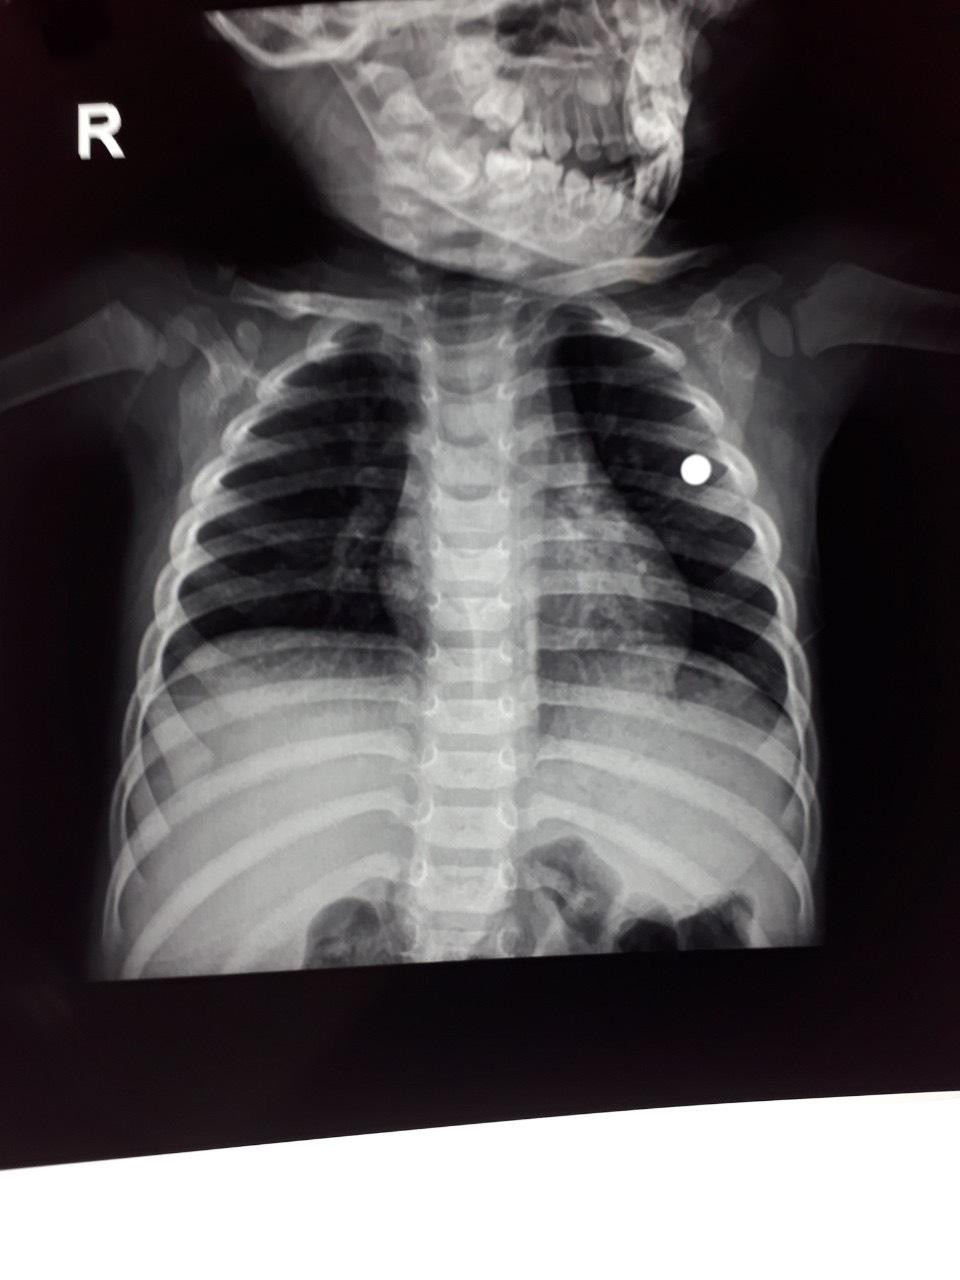

Theo thông tin từ gia đình bệnh nhân cho biết, ngày 18/2, trong quá trình chơi đùa, không may V. bị anh trai (5 tuổi) dùng súng cồn bắn vào ngực trái cạnh tim. Sau khi trúng đạn, cháu V. bị chảy máu nhiều, được đưa tới sơ cứu tại bệnh viện Đa khoa huyện Thường Xuân, rồi chuyển xuống bệnh viện Nhi Thanh Hóa cấp cứu. Các bác sĩ đã phẫu thuật lồng ngực trái gắp đạn ra. Tình trạng hiện tại bệnh nhân tỉnh táo, không còn nguy hiểm đến tính mạng.

| Viên đạn trong ngực trái của cháu bé. Ảnh do Bệnh viện Nhi Thanh Hoá cung cấp |